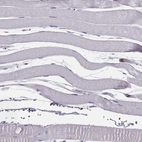

Immunohistochemistry analysis in human epididymis and skeletal muscle tissues using HPA001625 antibody. Corresponding PNP RNA-seq data are presented for the same tissues.